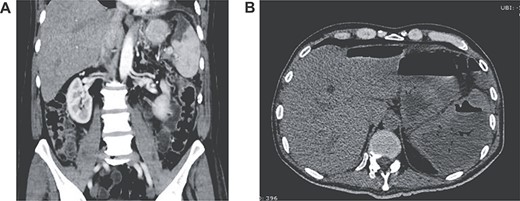

(A) Contrast-enhanced CT showing splenic infarction with inflammatory changes; (B) CT showing free liquid with a hypodense lesion.

Two weeks after discharge, he developed a high fever and acute abdominal pain in his upper left abdomen. Diffuse abdominal tenderness was detected and complementary exams revealed leukocytosis, neutrophilia, elevated C-reactive protein and increased levels of serum procalcitonin. Attributable to his background, a contrast-enhanced abdominal CT was requested detecting an enlarged spleen with a hypodense low-density lesion filled with gas. Free liquid was detected in the abdomen as well (Fig. 2A and B).